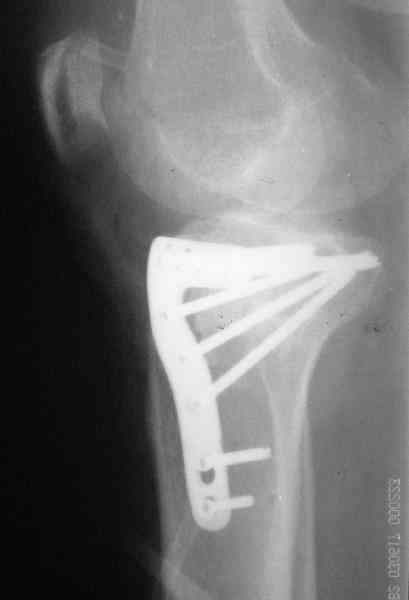

Уважаемый Абдурашид. Если нет противопоказаний , то из оперативных способов, я бы рекомендовал следующие: Полное замещение наружного мыщелка аллотрансплантатом либо открытая репозиция с элевацией и замещение дефекта ауто или аллокостью. В Ваших условиях , я бы рекомендовал второй способ. Во-время элевации необходимо разъединить фрагменты со стороны сустава ( надсечь скальпелем по линиям перелома, а затем тонким остеотомом их разъединить. При помощи долота произвести неполную остеотомию ( захватите не менее 1,5 - 2 см губчатой кости и поднять фрагменты, визуально отрепонировать и фиксировать 2-3 спицами. Дефект заместить костным ауто или аллатрансплантатом. Окончательная стабилизация пластиной ( лучше с угловой стабильностью, либо АВФ - позволит спокойно устранить угловую деформацию.